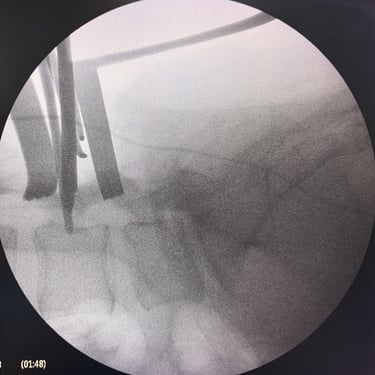

Manejo quirúrgico de la hernia lumbar con inestabilidad: enfoque moderno con FTP y TLIF

La hernia lumbar con inestabilidad vertebral es una patología frecuente que causa dolor lumbar persistente, ciática y limitación funcional, afectando la calidad de vida del paciente. Cuando el tratamiento conservador no logra resultados adecuados, la cirugía se convierte en la mejor opción terapéutica. La fijación transpedicular con tornillos (FTP) junto con la técnica TLIF (Transforaminal Lumbar Interbody Fusion) permite estabilizar la columna, descomprimir las estructuras nerviosas y lograr una adecuada fusión ósea. Este abordaje, especialmente mediante técnicas mínimamente invasivas (MISS), ofrece múltiples beneficios, como menor daño muscular, menor dolor postoperatorio y recuperación más rápida, facilitando el retorno temprano a las actividades cotidianas con mejores resultados clínicos.